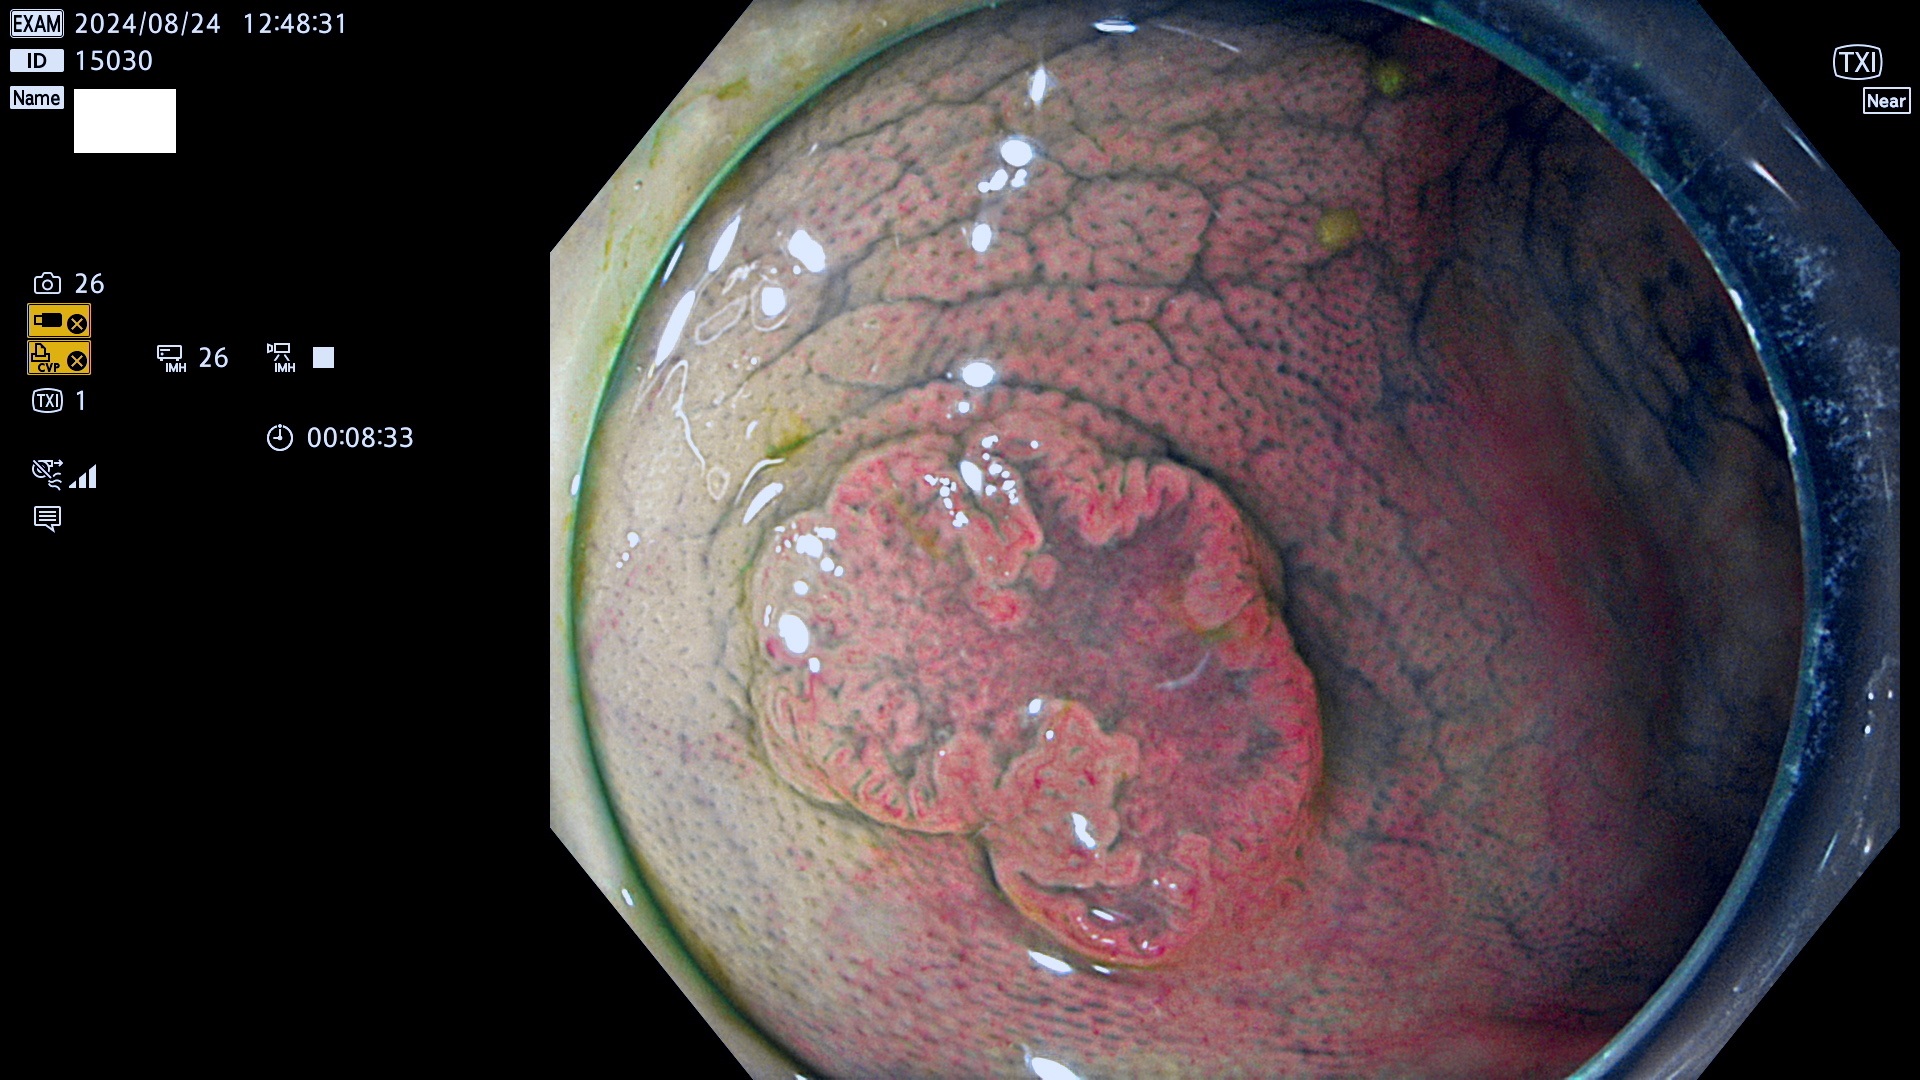

完全に平坦な物をUb、陥凹している物をUcと呼びます。最も発見が難しく危険な病変です。

毎週の検査(木・金・土・日)に発見されたUb、Uc型・腺腫を、その週の日曜の夜にUPし1週間、提示します。

抽出の対象期間 2024年8月22日〜8月25の4日間(33件の検査)7件 (7/33=21%)